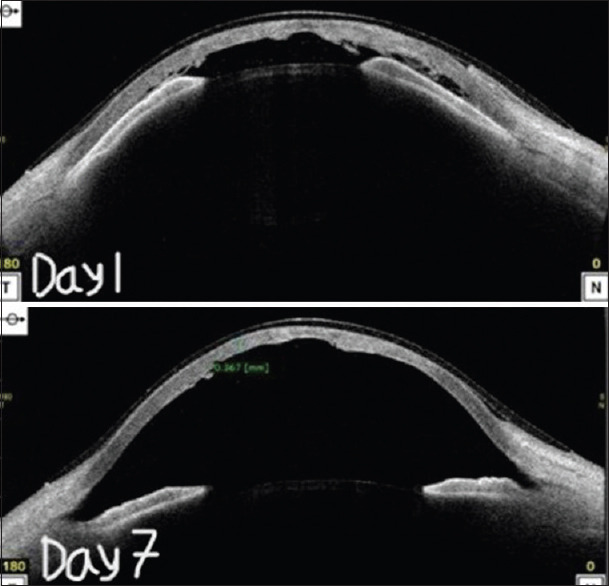

To describe the management of post-traumatic Descemet's membrane detachment and intraoperative corneal rupture in a known case of Ehlers-Danlos Syndrome (EDS). A 7-year-old child, a known case of EDS, presented with Descemet's membrane tear in the right eye for which intracameral sulfur hexafluoride (SF6) and descemetopexy were done. Intraoperative spontaneous rupture of the cornea was noted during descemetopexy which was managed using cyanoacrylate glue and bandage contact lens. We successfully used cyanoacrylate tissue adhesive glue for sealing of corneal rupture suggesting that it can be considered a treatment option for such cases where there is a lack of tissue strength for suturing.